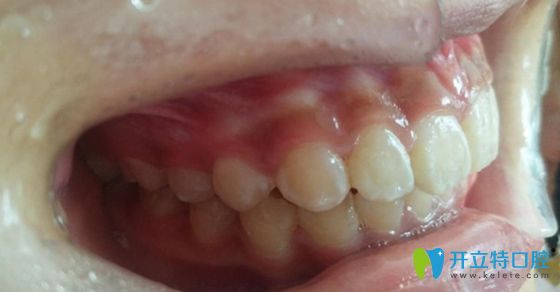

<標(biāo)準(zhǔn)的牙齒咬合圖片~>

如圖所示,這才是正常的咬合和牙齒排列位置嘛。不過,這兩張圖的主人可是同一人哦!想必大家也猜到了吧,是的,這就是小A經(jīng)歷兩年矯正生涯后的成果。

這前后差異也太大了吧,難怪那么多人都說“整牙堪比整容”。是該感嘆口腔醫(yī)學(xué)的發(fā)達(dá)呢,還是這位醫(yī)生的技術(shù)太贊呢,應(yīng)該兩者兼?zhèn)浒桑?/p>

<深覆合深覆蓋矯正好了!>